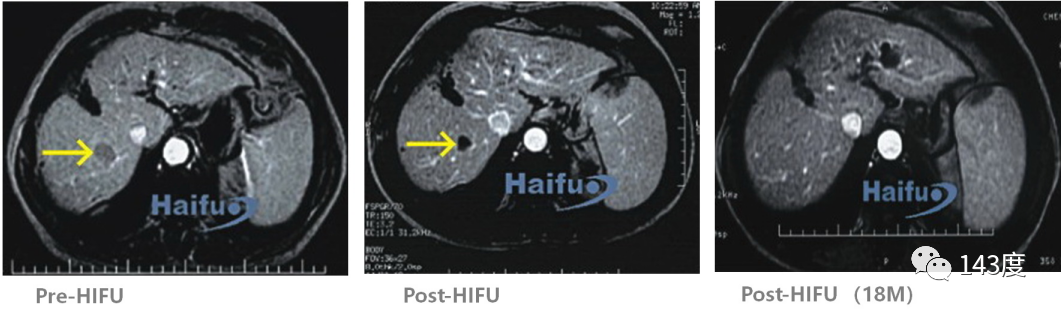

Liver Cancer Treatment Case 8:

Patient: Male, 58 years old, primary liver cancer

Recurrence observed after surgery for right lobe liver cancer. Complete tumor ablation achieved with HIFU treatment, confirmed by tumor absorption 18 months later.